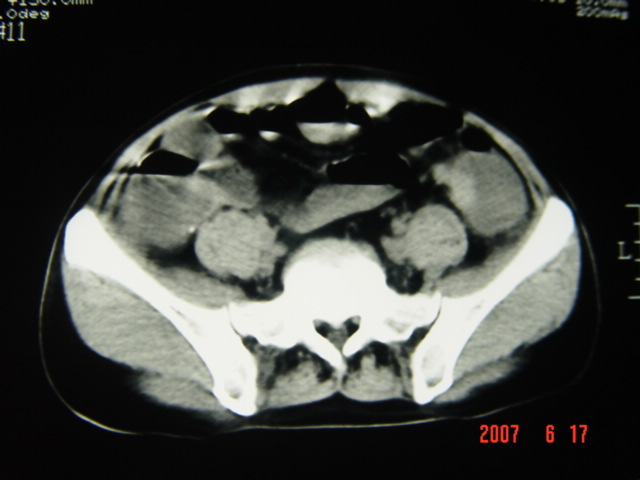

[br][br]以下是引用lkc8963在2007-6-17 13:32:00的发言:[br]完全支持邓主任意见:降/乙交界部占位性病变伴不全梗阻.做个增强或者be可能更好.